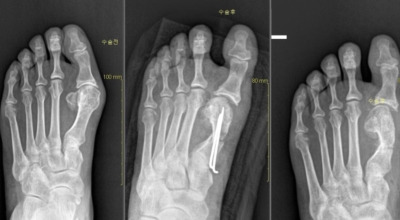

보존적 치료는 변형이 심하지 않은 경우에 우선적으로 고려되는 방법입니다. 굽이 높은 신발이나 발끝이 좁은 신발을 피하고, 편안한 신발을 착용해 발에 가해지는 압박을 최소화합니다. 또한, 신발 안에 중족골 패드나 발가락 교정기 등의 교정 도구를 사용해 압력을 재분배하고 증상을 완화시킵니다. 만약 보존적 치료로 증상이 개선되지 않거나 통증이 매우 심할 경우, 수술을 고려할 수 있습니다.

초기 단계에서는 건막류(두꺼운 혹)를 제거하는 건막류 절제술을 시행합니다. 이 수술은 돌출된 건막류를 제거하여 각도를 교정하고, 짧아진 근육이나 연부조직을 늘려주는 비교적 간단한 수술입니다. 만약 다른 발가락의 변형이 함께 있거나 뼈의 과잉 성장이 심한 경우, 뼈를 깎아 방향을 수정하고 발가락을 똑바로 펴기 위해 철사로 고정하는 교정 절골술을 시행합니다. 양쪽 발이 모두 변형된 경우 대부분 한쪽씩 나누어 수술을 진행합니다.